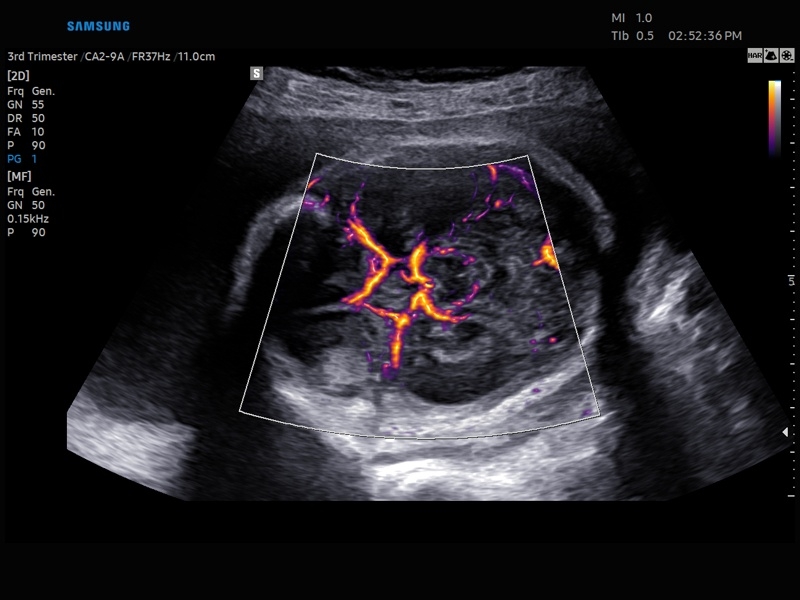

Ультразвуковой сканер V8-RUS является экспертным классом (премиальный уровень) и производится компанией Samsung Medison. Сканер V8 обеспечивает превосходное качество изображения благодаря использованию технологии Crystal Architecture™, которая включает в себя передовое аппаратное обеспечение, монокристальную технологию изготовления датчиков и сложную программную обработку ультразвуковых лучей.

Samsung Medison V8 представляет собой современную ультразвуковую систему, в которой воплощен многолетний опыт компании Samsung в создании эргономичного и интеллектуального диагностического оборудования. Система оснащена передовыми инструментами автоматизации, которые значительно упрощают рабочий процесс и повышают эффективность исследований.

Система Samsung Medison V8 обеспечивает высококачественную диагностику в различных областях медицины:

• Абдоминальные исследования

• Акушерство и гинекология

• Модуль MV-Flow – программа (режим), позволяющая визуализировать кровоток в микроциркуляторном русле с высоким разрешением без использования контраста.

• Модуль LumiFlow – программа отображения кровотока с объемной графикой для лучшего понимания архитектоники сосудистого русла.